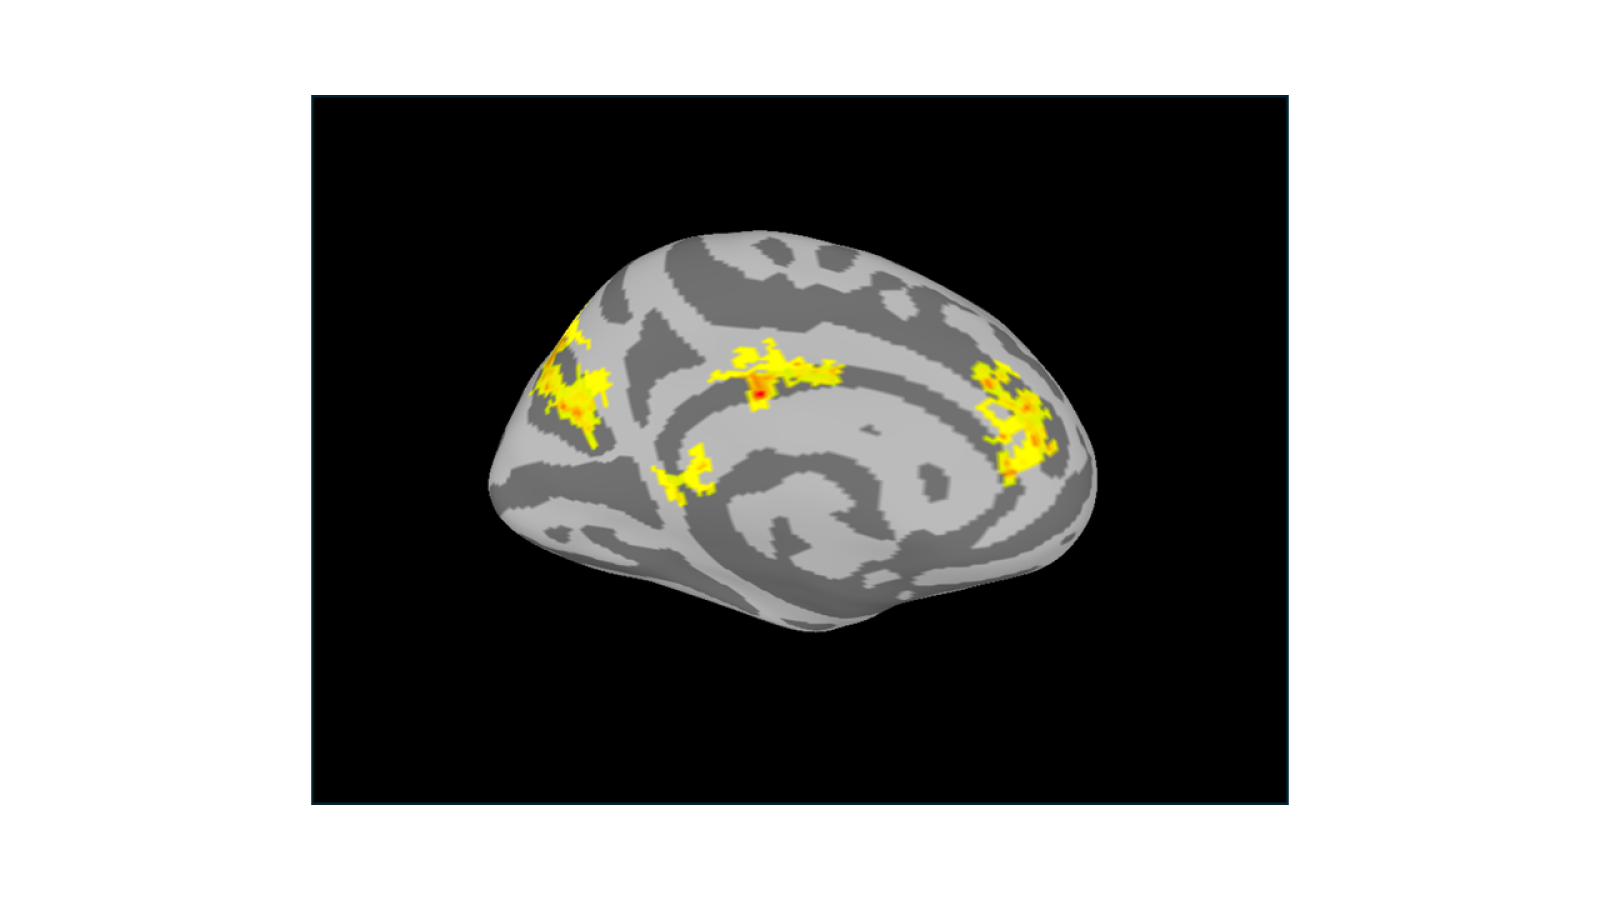

What does the brain look like when we “like” something? When people bid real money for their favorite snacks, some brain areas light up more for higher bids. From right to left, this image highlights the medial prefrontal cortex, cingulate cortex (the two spots in the middle), and parietal cortex — key parts of the brain’s value network that help us decide what something is worth.